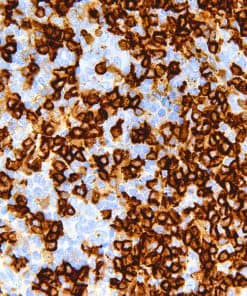

Thymidylate Synthase

Thymidylate Synthase (TS) is a crucial enzyme responsible for the synthesis of 2′-deoxythymidine-5′-monophosphate (dTMP) a precursor for thymidylate which is necessary for DNA replication and repair from 2′-deoxyuridine-5′-monophosphate (dUMP). In terms of cancer, TS is an important target for cancer treatment as the inhibition of TS and therefore nucleotide synthesis necessary for cell growth has shown to be a vital part for successful treatment against colorectal, pancreatic and breast cancers.

| Clone | IHC697 |

| Source | Mouse Monoclonal |

| Positive Control | Colon Cancer |

| Dilution Range | 1:100 – 1:400 |